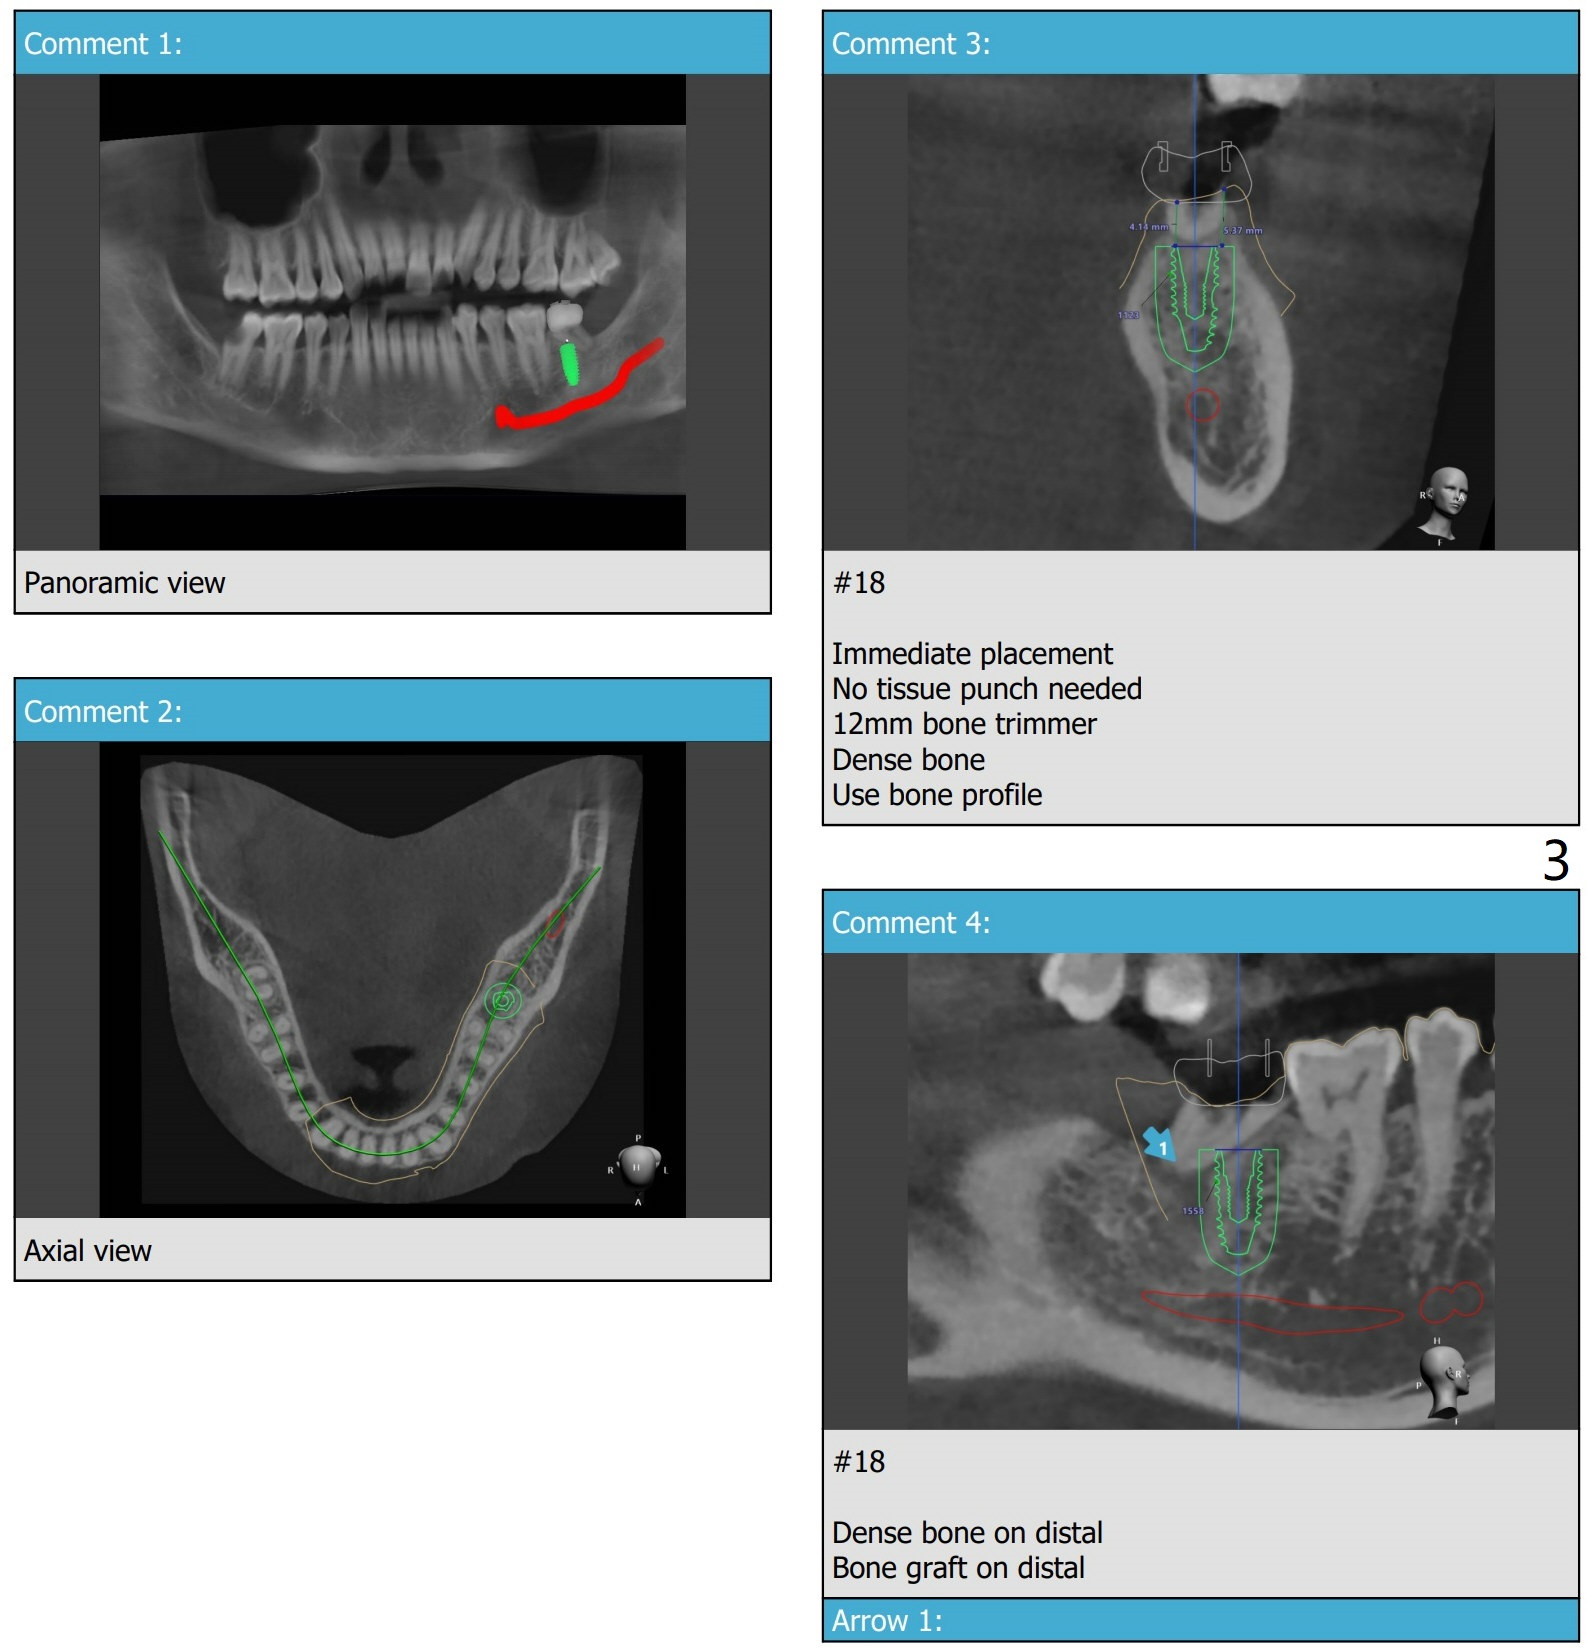

左下7植体设计

先将2.2mm钻头逐渐抵达深度,拍摄根尖片,完成种植和放置基台后,再拍摄根尖片,比较是否钻洞偏移远中。植体植入稍微浅些。